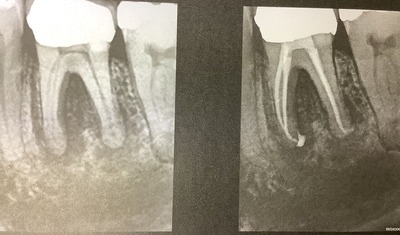

根管充填3ヶ月後に検診した。

根管治療の経過

6ヶ月後のレントゲンでは根っこに影はあったが、大きくはなっていない。

特に症状も変化ないので、そのまま経過を観察した。